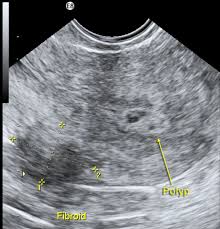

Endometrial Polyp Icd-10 / Endometrial Polyps At Hysteroscopy / A systematic review of 17 observational studies including over 10.. Below are 46 working coupons for endometrial polyp icd 10 code from reliable websites that we have updated for users to get maximum savings. In asymptomatic women, endometrial polyps may regress spontaneously, in symptomatic women endometrial polyps can be treated safely and efficiently with hysteroscopic excision. Menometrorrhagia, endometrial polyp, follicular cysts of left ovary. Please note that this database does not guarantee reimbursement. An endometrial polyp or uterine polyp is a mass in the inner lining of the uterus.

They may have a large flat base (sessile) or be attached to the uterus by an elongated pedicle (pedunculated). Uterine polyps, also called endometrial polyps, are small, soft growths on the inside of a woman's uterus, or womb. They may have a large flat base (sessile) or be attached to the uterus by an elongated pedicle (pedunculated). More information on how to use the online browser is available in the help. Endometrial polyp in an aged rhesus macaque, macaca mulatta.

Endometrial blight inspection moreover analysis. This lining grows and shrinks during different stages of the menstrual cycle. More information on how to use the online browser is available in the help. Transcervical reseksjon av endometriereseksjon hos postmenopausale kvinner. Menometrorrhagia, endometrial polyp, follicular cysts of left ovary. They come from the tissue that lines the uterus, called the endometrium. In asymptomatic women, endometrial polyps may regress spontaneously, in symptomatic women endometrial polyps can be treated safely and efficiently with hysteroscopic excision. Endometrial polyps are overgrowths of endometrial glands that typically protrude into the uterine cavity. An endometrial polyp or uterine polyp is a mass in the inner lining of the uterus. They may have a large flat base (sessile) or be attached to the uterus by an elongated pedicle (pedunculated). 68.22 incision or excision of congenital septum of uterus. A subtotal abdominal hysterectomy (salvaging the cervix) with bilateral. Are you looking for endometrial polyp icd 10 code?

The incidence rises steadily with increasing age, peaks in the fifth the great majority of endometrial polyps are benign, but malignancy occurs in some women. An endometrial polyp or uterine polyp is a mass in the inner lining of the uterus. Endometrial polyps can either be sessile or pedunculated. People who have had polyps in the past are somewhat more likely to develop them in the future, compared to uterine polyps have roughly a 5 percent chance of being related to cancer (malignant), while fibroids have less than a 1 percent likelihood of malignancy.410. The uterus is primarily made up of muscle fibers but has an inner lining made up of endometrial tissue.

International statistical classification of diseases and related health problems 10th revision. They may have a large flat base (sessile) or be attached to the uterus by an elongated pedicle (pedunculated). They can range in size from as small as a sesame seed to as big as a golf ball. They can often be suggested on u. The diagnoses for this patient are: Endometrial polyps are rare among women younger than 20 years of age. They may have a large flat base (sessile) or be attached to the uterus by an elongated pedicle (pedunculated). In asymptomatic women, endometrial polyps may regress spontaneously, in symptomatic women endometrial polyps can be treated safely and efficiently with hysteroscopic excision. Polypoid endometrial hyperplasia ( n85.0. Endometrial polyps can either be sessile or pedunculated. Endometrial polyps, which are sessile or pedunculated projections of the endometrium, develop as solitary or multiple soft tumors, which are usually stromal but in some cases composed of hyperplastic endometrium figure 10.15. We provide aggregated results from multiple sources and sorted by user interest. You can always come back for endometrial polyp icd 10 code because we update all the latest coupons and special deals weekly.